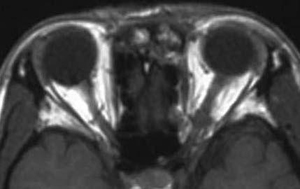

Ⅰ 30歳代女性

左眼窩尖端部腫瘍、病理診断は神経線維腫。

左視力、視野障害を主訴として来院した。摘出手術後視力、視野障害は正常化した。

• 術後MRI